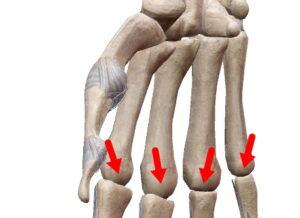

楕円関節

| 球関節の楕円バージョン。楕円なので回旋は出来ない2軸の関節。環椎後頭関節、橈骨手根関節、中手指節関節(母指以外)。 |